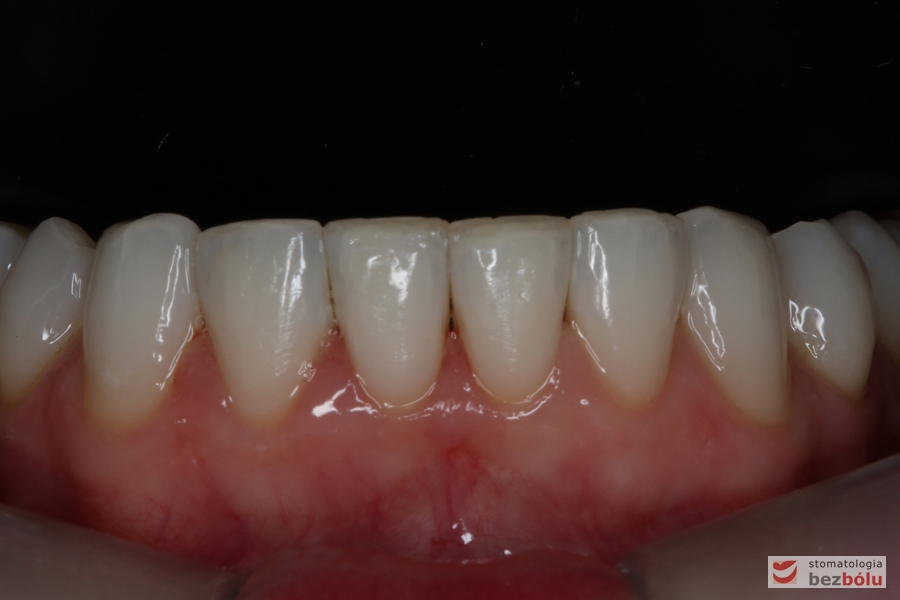

Uszeregowane siekacze dolne - tork dodatni

Uszeregowane siekacze dolne – tork dodatni